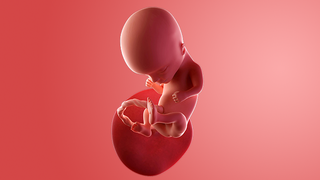

What does my baby look like?

Your baby, or foetus, is around 7.4cm long, which is about the size of a peach.

Your baby's ovaries or testes are fully developed inside and final tweaks are being made on the outside.

The baby is moving around. At first the movements are very jerky and random but then they start to look more deliberate. You may not feel any movement until around week 17.

Some babies suck their thumb in the womb. This actually serves a purpose as it helps to develop their sucking reflex. They'll need this when it comes to feeding.